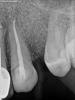

Magdalena Опубликовано 3 марта, 2013 Поделиться Опубликовано 3 марта, 2013 (изменено) По снимку все вроде нормально запломбировано. Болеть может при трещине корня от анкерного штифта (трещину на прицельном снимке редко можно распознать, на КТ можно увидеть), при трещине характерная боль в зубе при разжатии челюстей. Может болеть от оставшихся микробов или от немного выведенного материала за верхушку корня, сложно сказать.А с соседними зубами все в порядке? У Вас есть панорамный снимок? Изменено 3 марта, 2013 пользователем Magdalena Ссылка на комментарий

hauff Опубликовано 30 марта, 2013 Автор Поделиться Опубликовано 30 марта, 2013 Вот сделал пару картинок, первая 23, вторая 26. Не знаю правильно или нет. Всё же надеюсь что кто-нибудь скачает КТ и посмотрит http://s001.radikal.ru/i194/1303/c7/a81e85c48551t.jpghttp://s020.radikal.ru/i702/1303/68/bcb508263600t.jpg Ссылка на комментарий

Мартовский Опубликовано 30 марта, 2013 Поделиться Опубликовано 30 марта, 2013 Мне одному кажется что 23 вообще пустой? Это судя по скриншоту, я кт не могу загрузить Хотя на срезахх устьев вроде все нормально. Коллеги, у кого инет скоростной, посмотрите пожалуйста, у меня такой объем инфы не загружается. Ссылка на комментарий

АнтонТЛТ Опубликовано 30 марта, 2013 Поделиться Опубликовано 30 марта, 2013 По скриншоту 23 запломбирован. См. 3д моделирование и в осевой проекции. В 26 возможно есть мб2, форма мб корня в вестибуло-оральном направлении продолговатая. Подождем пока кто-нибудь загрузит кт и нарежет слайды. Сижу с телефона, возможности скачать нет Ссылка на комментарий